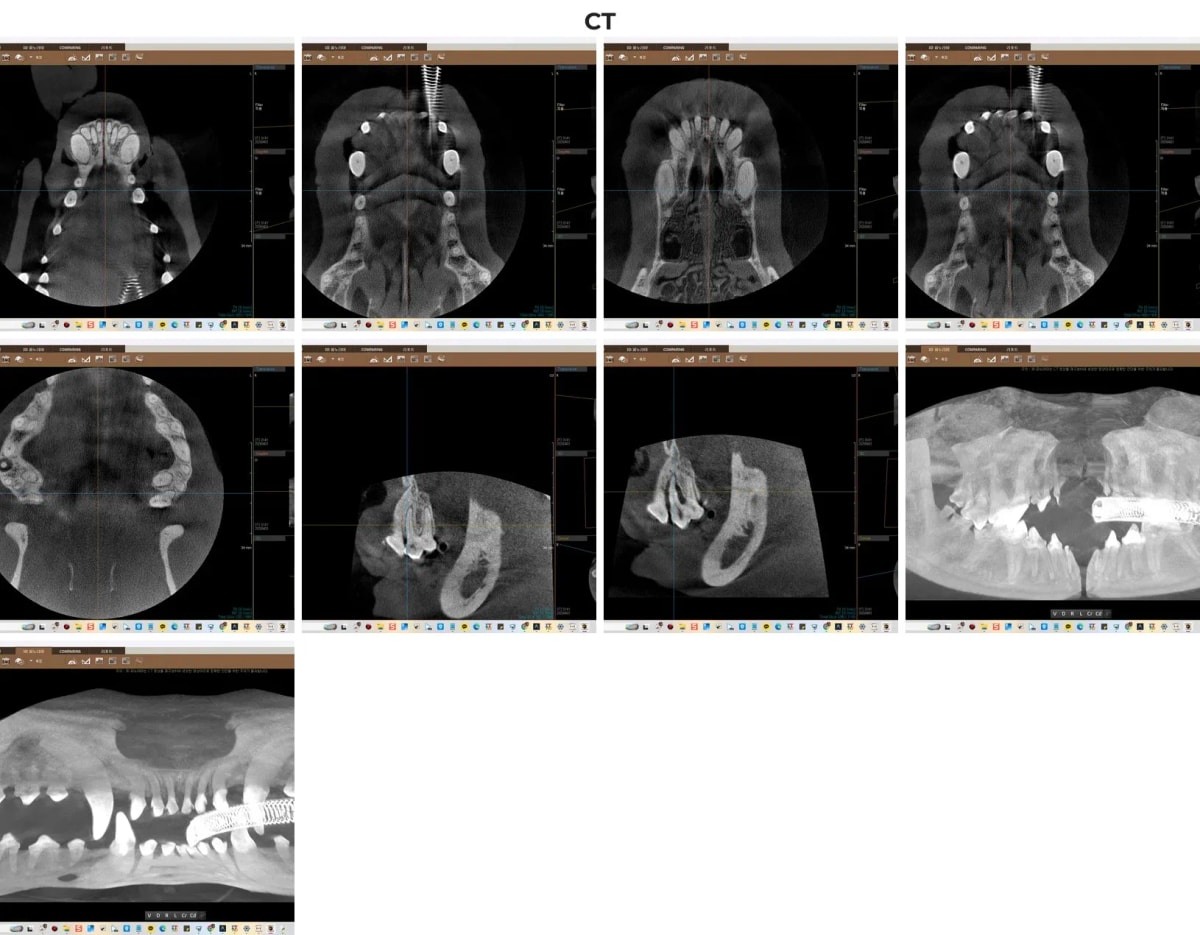

2. 보이지 않는 병변을 찾는 광주·전남 유일 치과 CT

정확한 치료 계획을 세우기 위해서는 겉으로 드러난 치석뿐만 아니라 잇몸 안쪽의 뼈 상태를 입체적으로 확인해야 합니다.

ℹ️ 치과 전용 CT의 중요성

광주 동물병원 중에서도 본원이 보유한 치과 전용 CT는 일반 엑스레이로는 확인하기 어려운 미세한 치조골 흡수(잇몸뼈가 녹는 현상)의 깊이와, 치아 뿌리 주변의 염증 상태를 3D 영상으로 완벽하게 구현해 냅니다. 특히 비전이처럼 다수의 치아 보존을 목표로 할 때는 CT 검사가 필수적입니다.

치과 전용 CT를 통한 비전이의 치조골 및 치아 뿌리 정밀 진단 영상